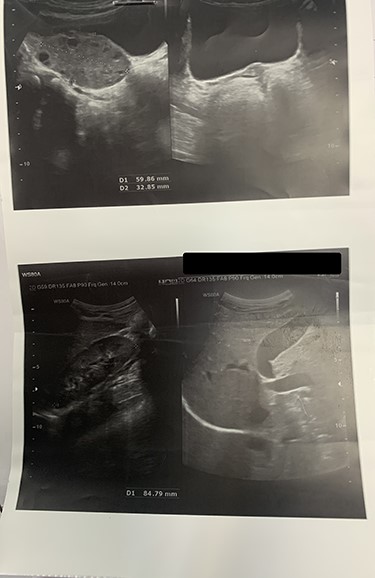

Based on a high probable diagnosis of ovarian torsion, surgical exploration was accomplished demonstrating bilaterally rudimentary or aplastic uterus, unilateral hypoplasia of the left adnexa, and torsion of the right ovary containing a simple cyst. Since the right utero-ovarian ligament was longer than normal size, the right adnexa was twisted and dislocated in the left lower quadrant, so the radiologist misreported torsion of the left adnexa (instead of the right side) (Fig. 2).

Findings of laparotomy: Torsion of right ovary and hypoplasia of the left adnexa. Uterus cannot be seen. Note the long ligament of the right ovary.